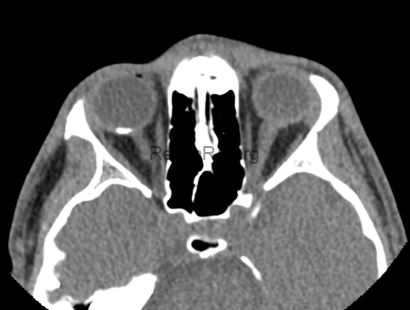

The axial orbital CT scan shows a hyperdense, plaque-like lesion located in the posterior aspect of the globe, along the choroid. The density of the lesion is comparable to cortical bone, confirming ossification typical of choroidal osteoma. The lesion does not appear to invade adjacent orbital structures or cause globe deformation. CT imaging is crucial for differentiating osteoma from other amelanotic intraocular lesions due to its ability to directly visualize calcification.